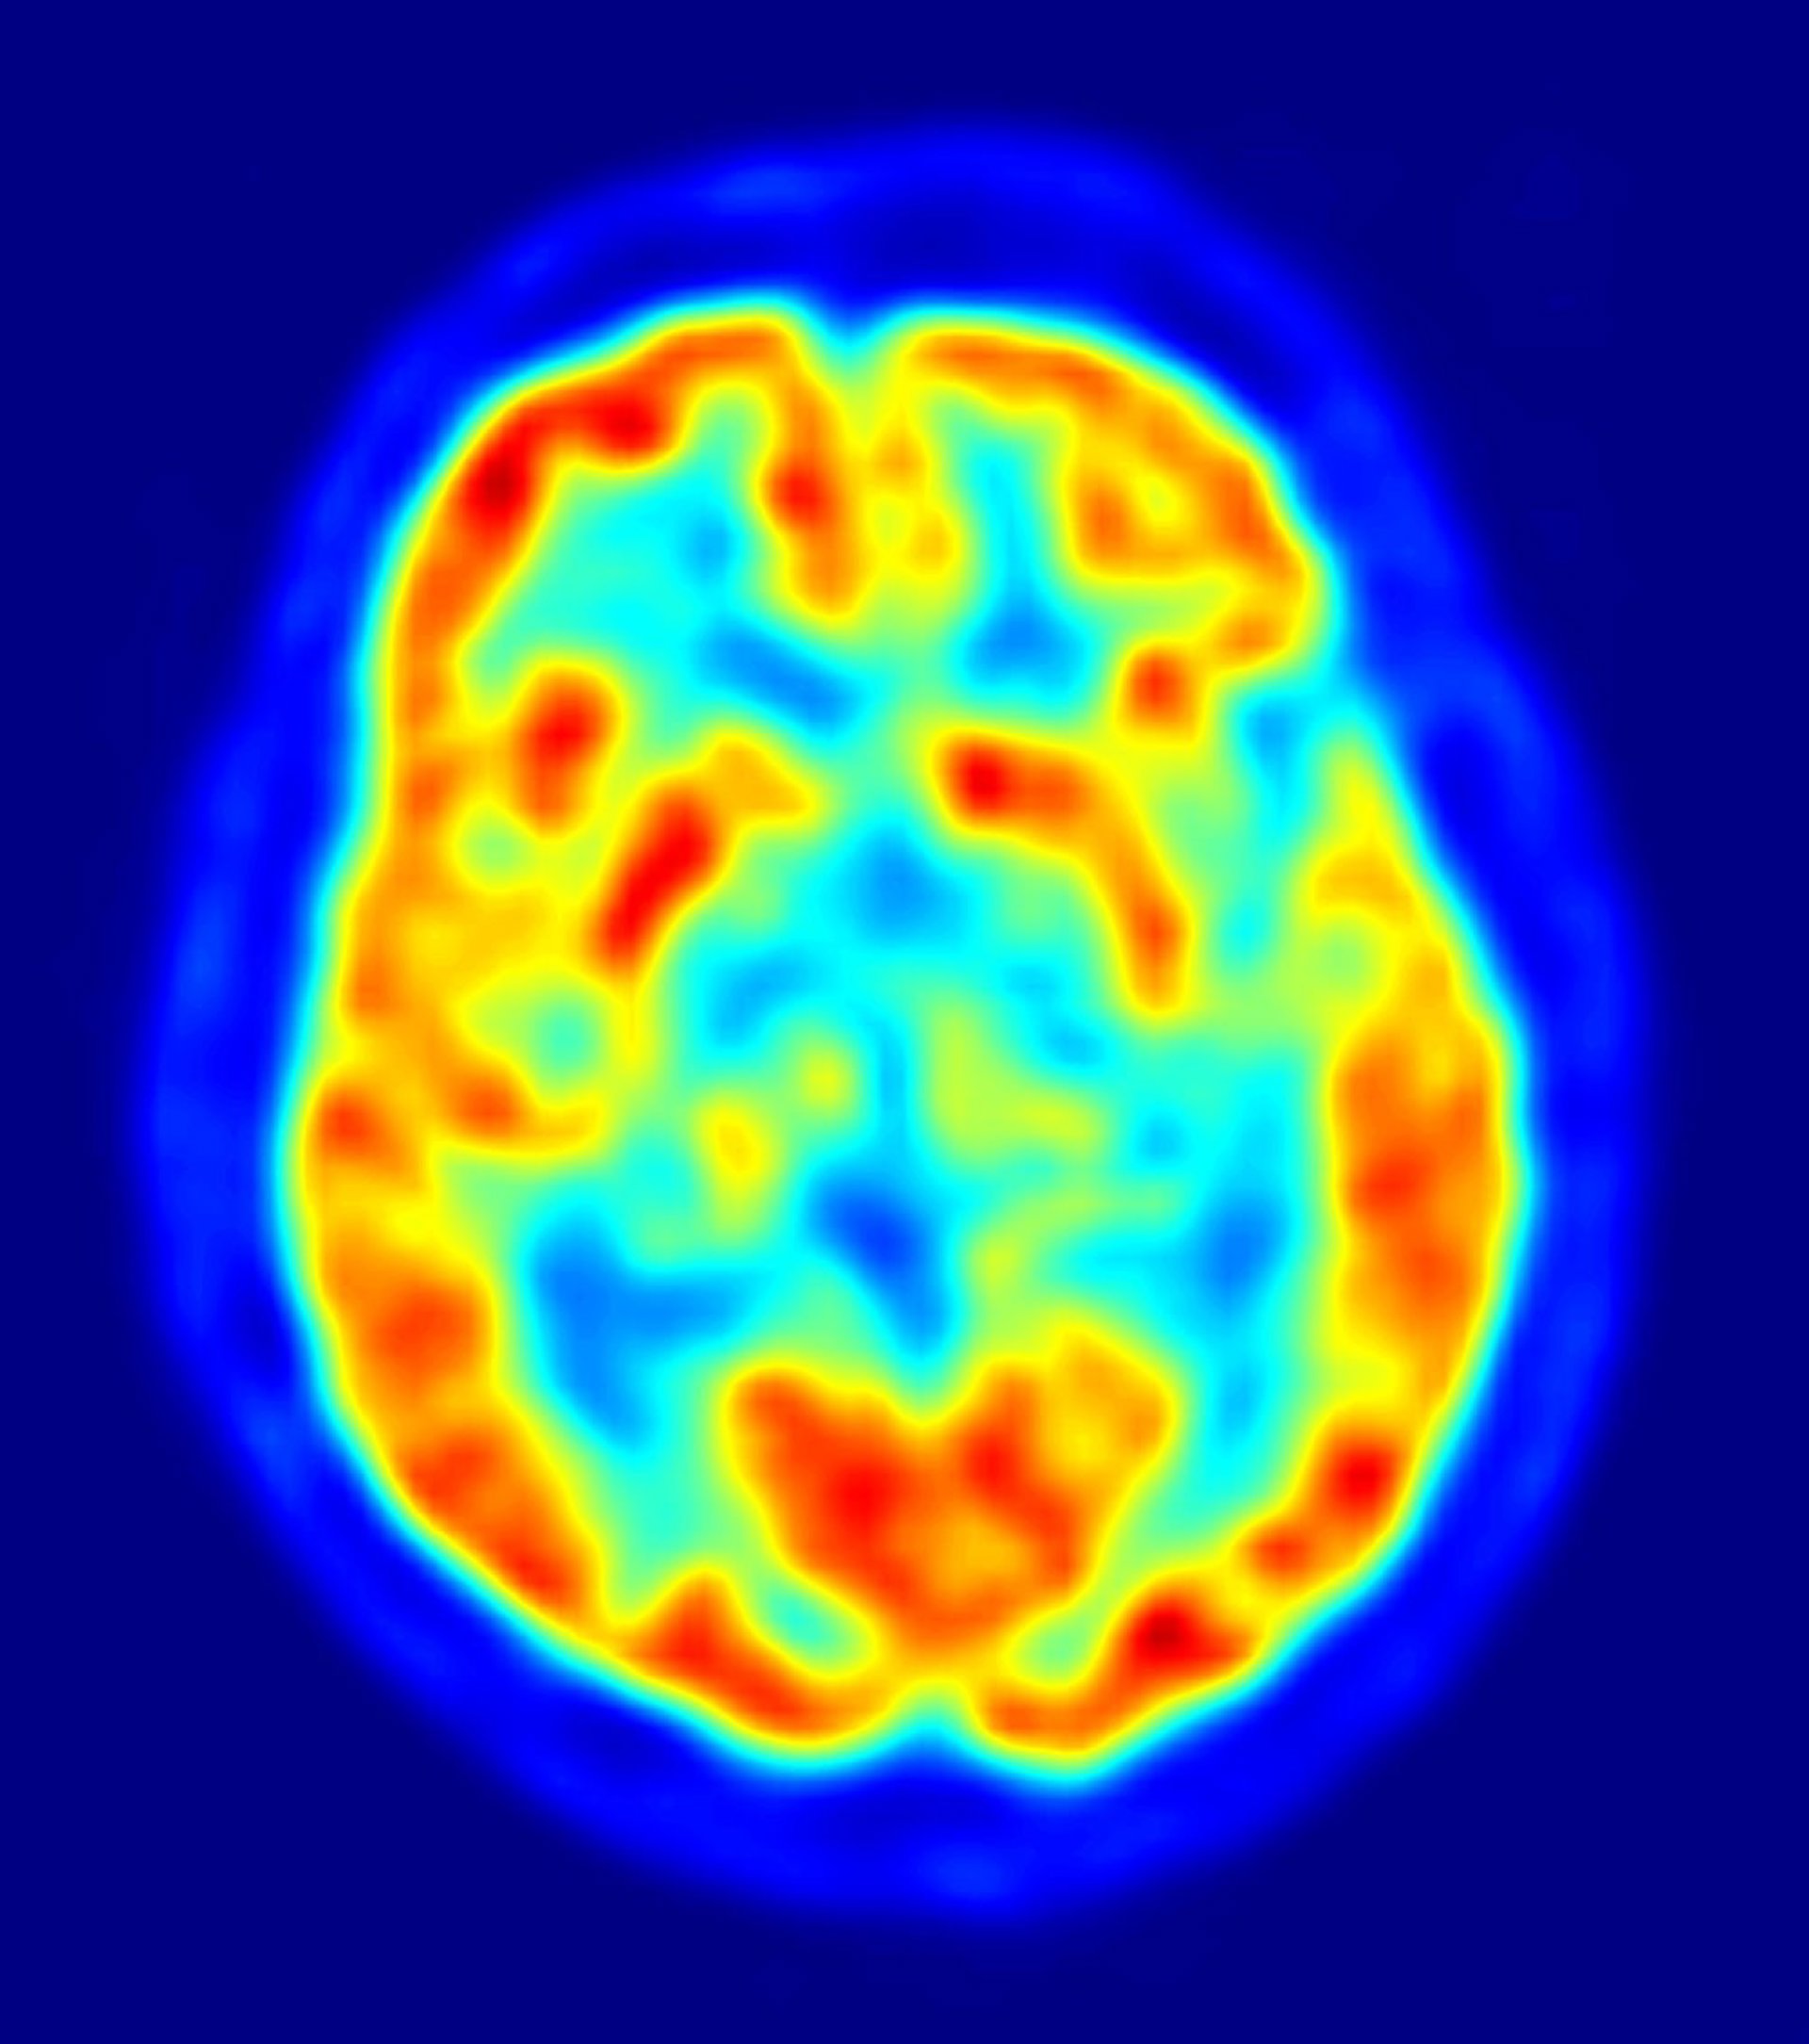

Las diferencias en el comportamiento altruista están relacionadas con la variación en el tamaño y la actividad de una región del cerebro involucrada en la empatía, según un estudio publicado en la revista 'Neuron'. Los resultados también proporcionan una explicación sobre por qué las tendencias altruistas se mantienen estables en el tiempo.

Las personas con facilidad para comprender a los demás son más altruistas; esta capacidad para comprender las perspectivas de otros ha sido previamente asociada con la actividad en una región del cerebro, conocida como unión temporoparietal (TPJ, por sus siglas en inglés). Basándose en estos hallazgos anteriores, Fehr y su equipo se dispusieron a analizar la relación entre el tamaño y la activación de TPJ, y las diferencias individuales en el altruismo.

En el nuevo estudio, los investigadores sometieron a los sujetos a un escáner de imagen cerebral, y les plantearon un juego en el que tenían que decidir cómo repartir dinero, entre ellos mismos y socios anónimos. Los sujetos que tomaron las decisiones más generosas mostraban un TPJ más grande, en el hemisferio derecho del cerebro, en comparación con los sujetos que tomaban las decisiones más egoístas.